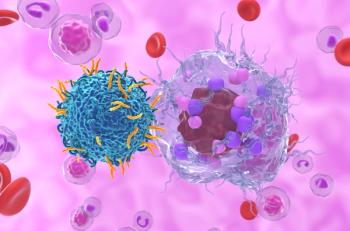

An RNA- and lipid nanoparticle–based platform derived from non-LTR transposons enables stable in vivo CAR T-cell engineering.